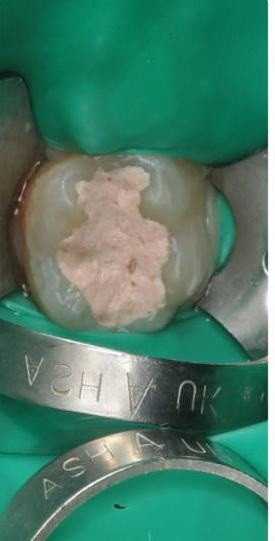

4 работы в портфолио